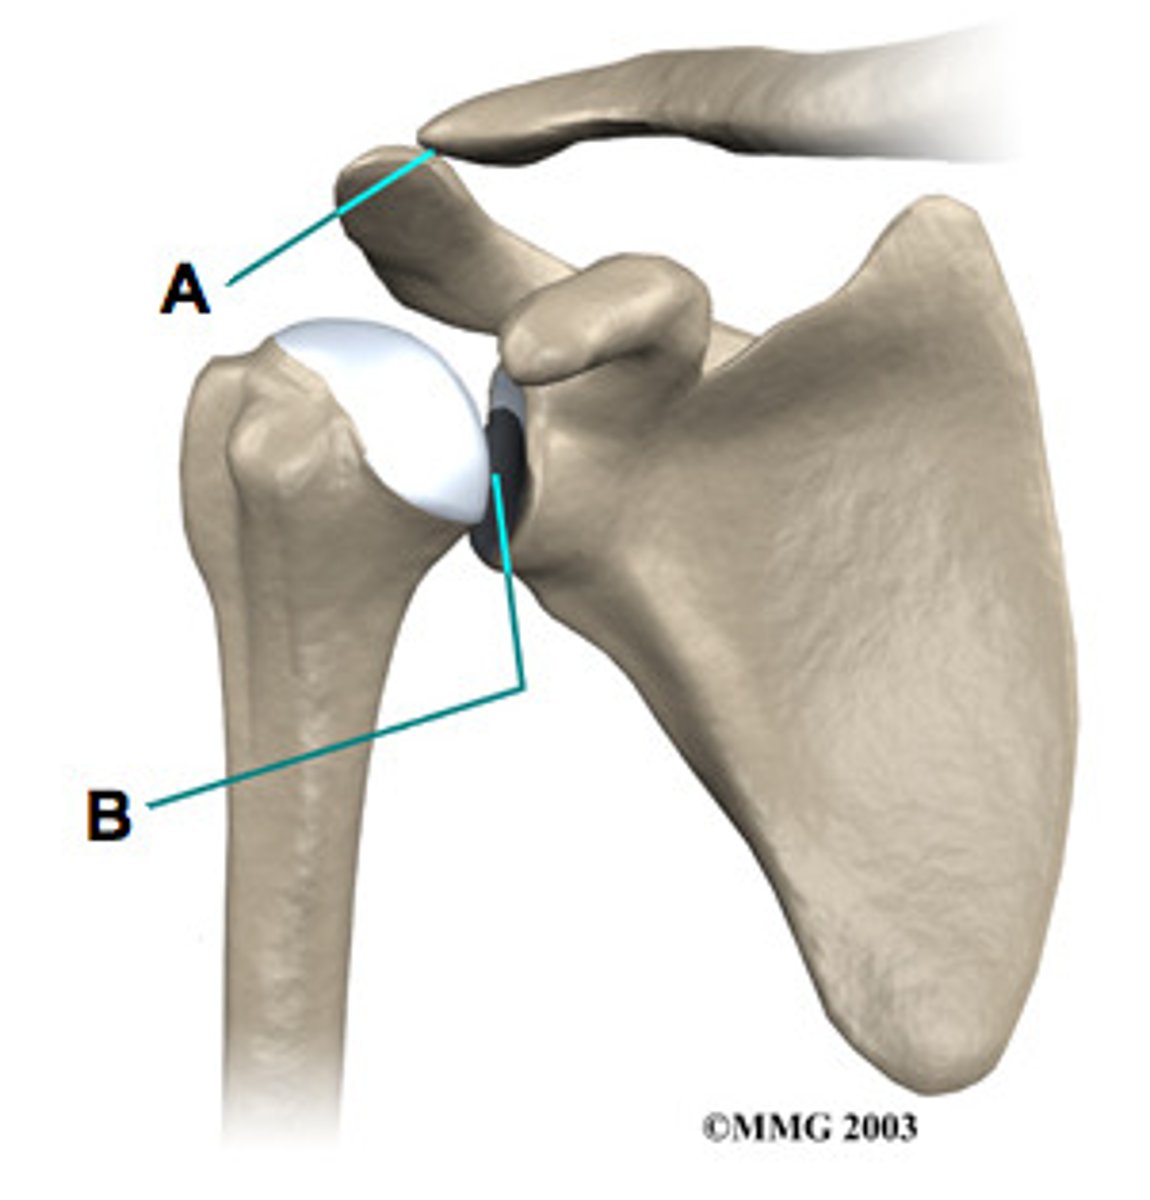

acromioclavicular j., sliding

Whats the name of joint A? and what type of joint is it?

glenohumeral j. , Ball & socket

What is B? and what type of joint is it?